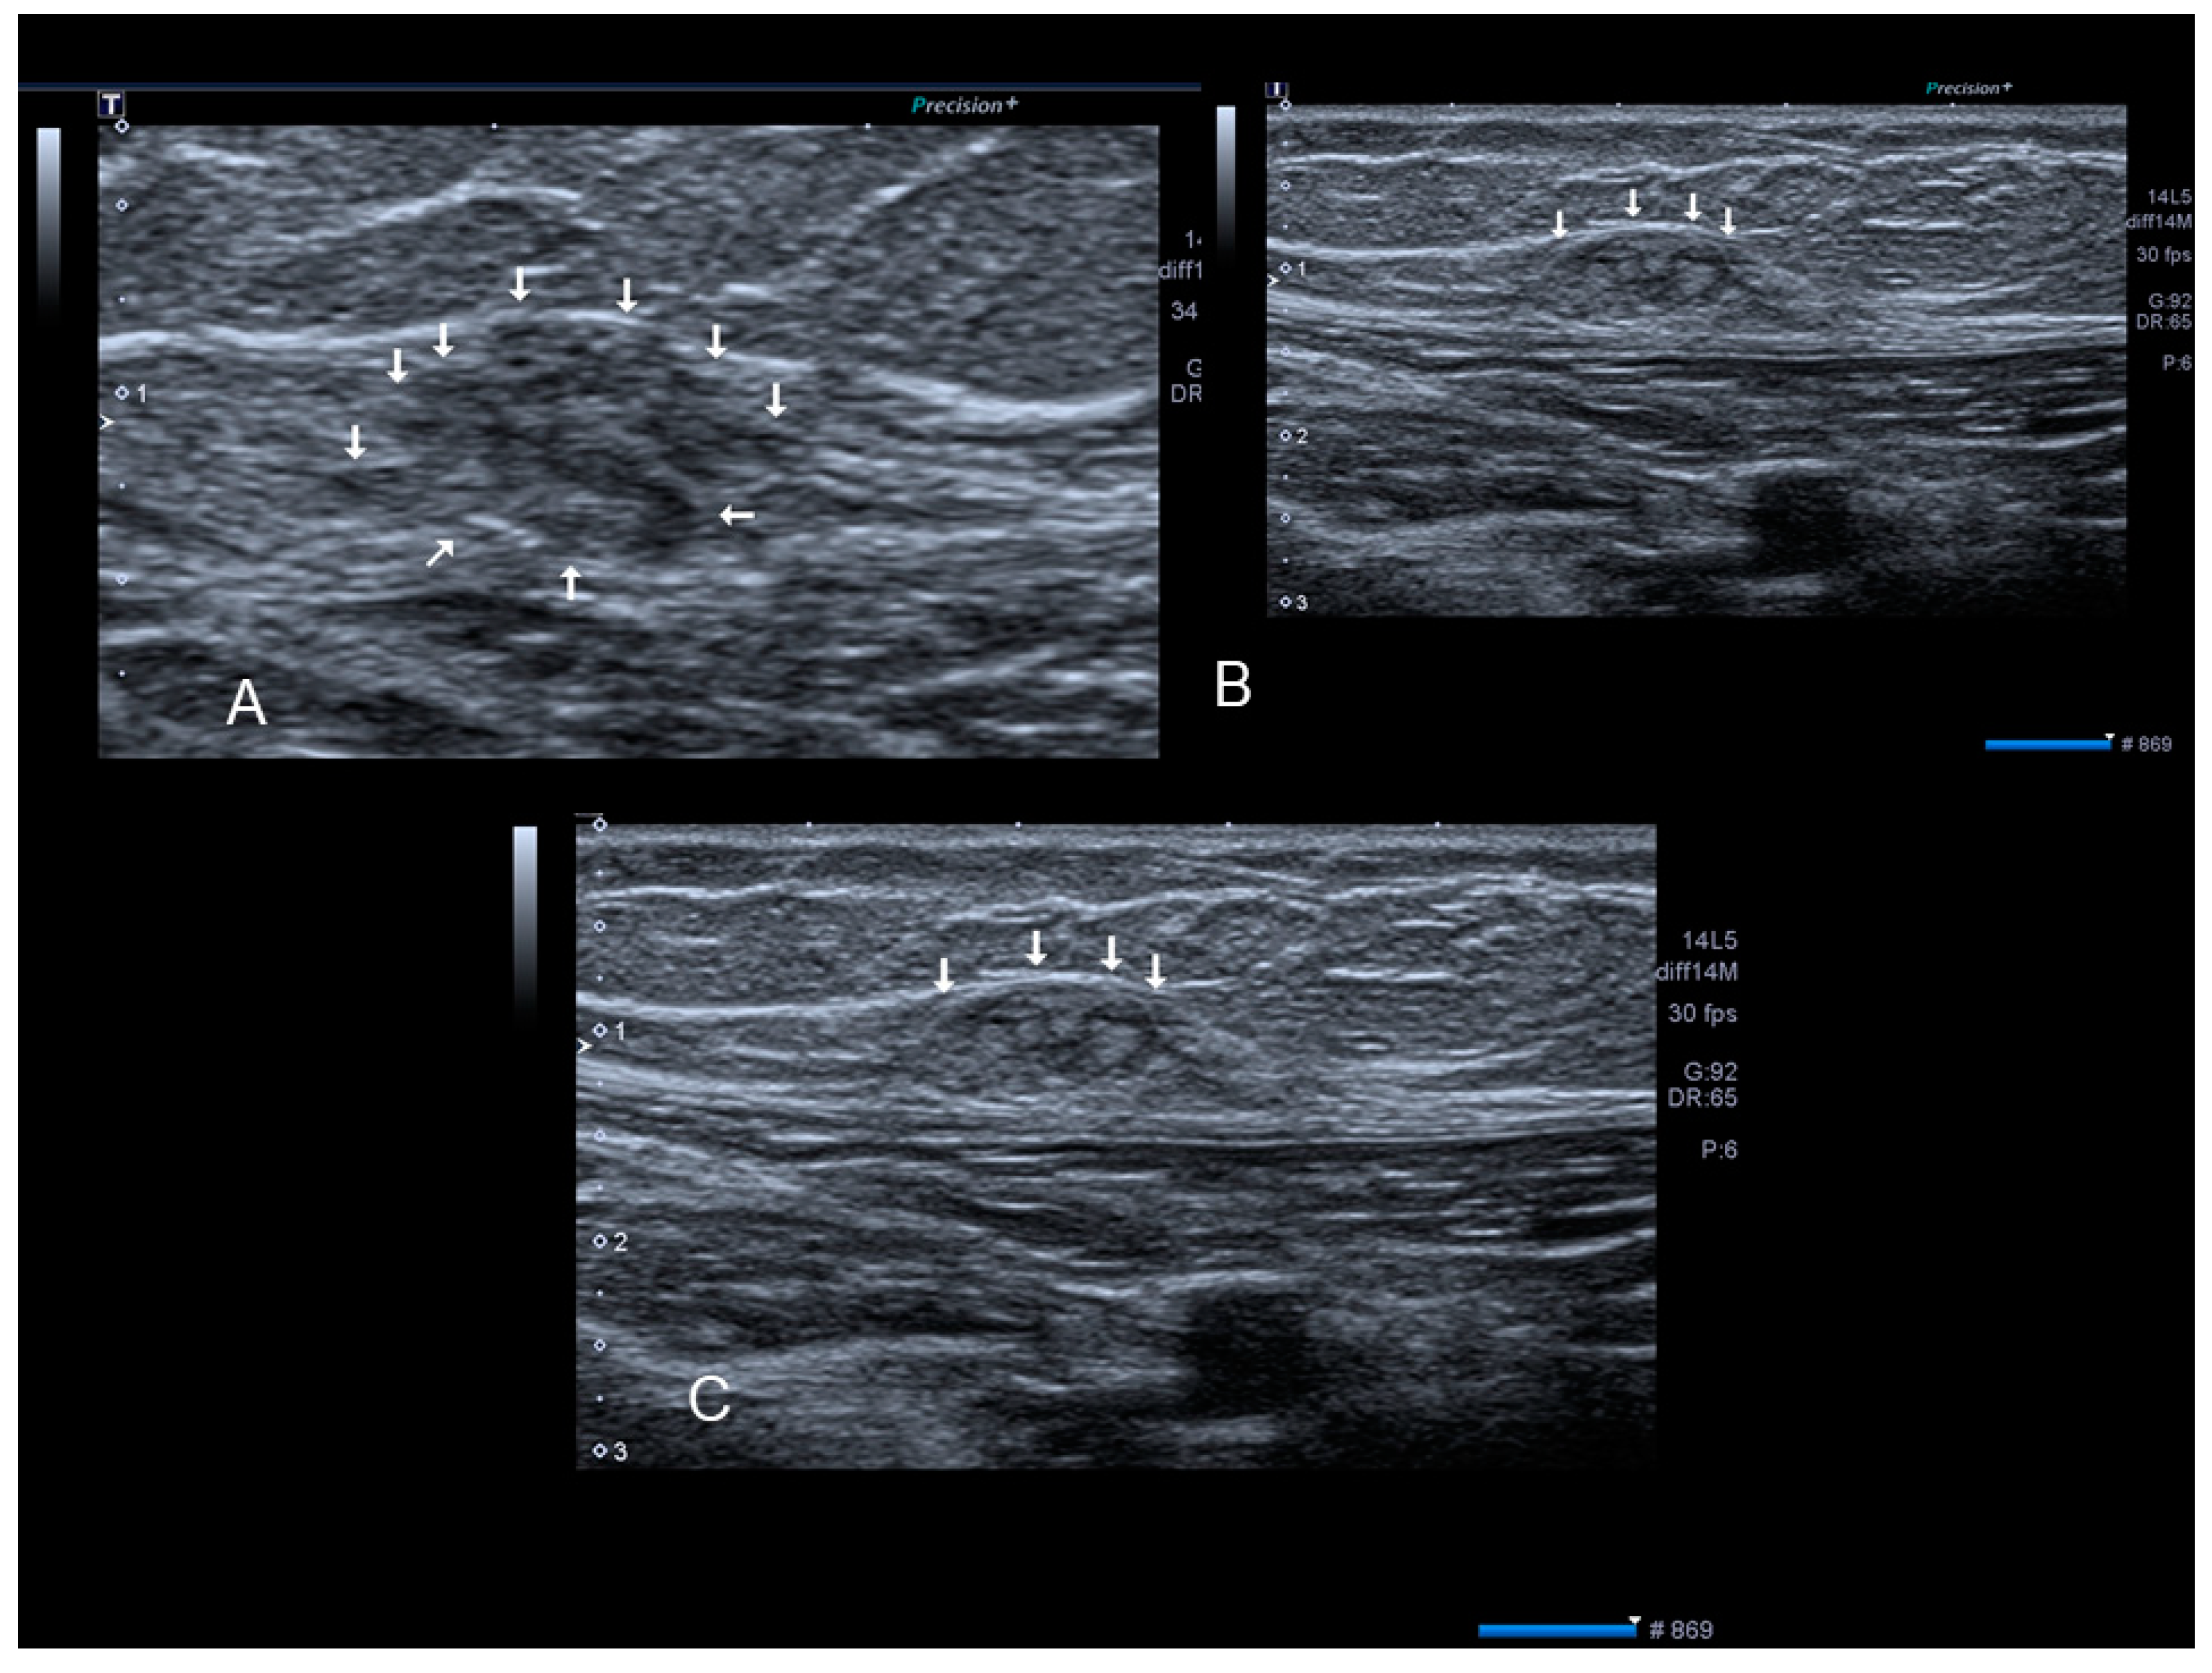

Bowel Endometriosis Symptoms Why Does Endo Masquerade As Ibs Dr S

Bowel Endometriosis Symptoms Why Does Endo Masquerade As Ibs Dr S from www.drseckin.com